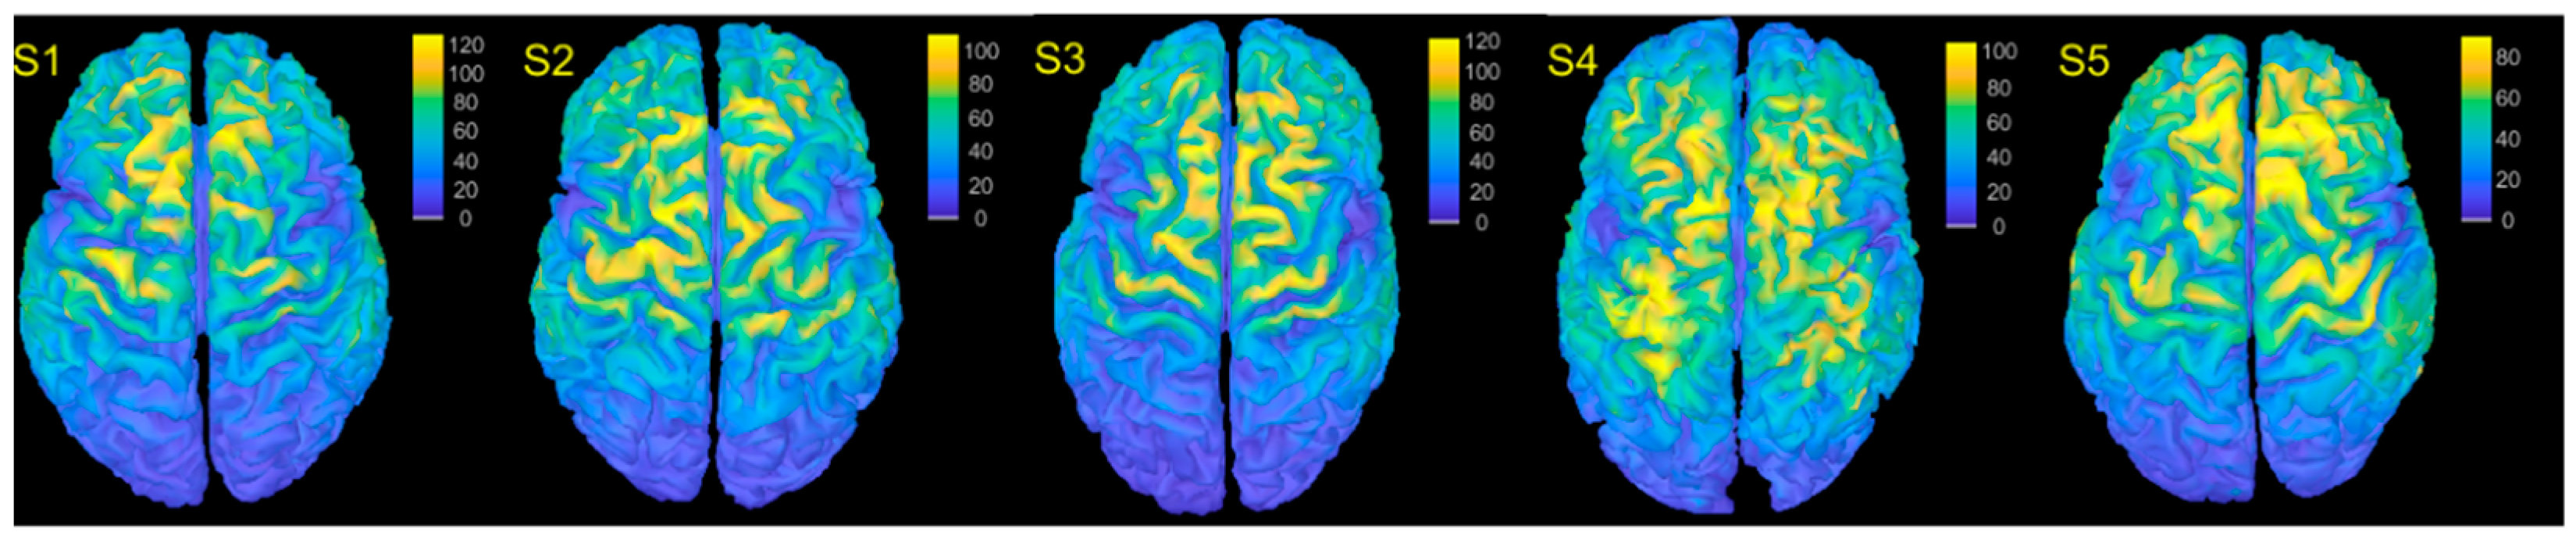

3.1. E-Field Estimation